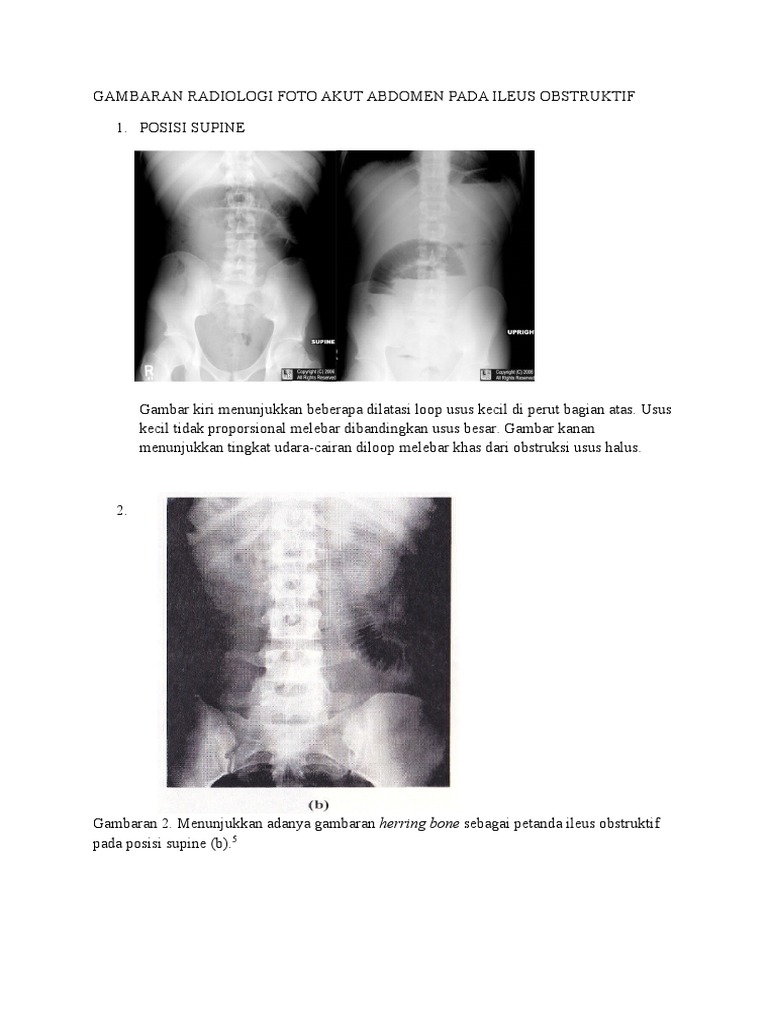

Gambaran Radiologi Ileus

Gambaran Radiologi Ileus www.scribd.com

ileus radiologi gambaran